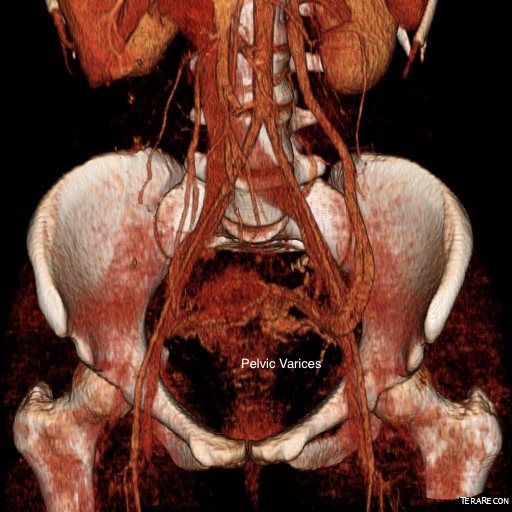

On examination, she was tender over the left kidney and flank. Laboratory examination was positive for microscopic hematuria. CT venography (below) showed an obstruction of her left renal vein by the superior mesenteric artery. Drainage via gonadal vein was not demonstrated, and no pelvic varices or complex of retroperitoneal veins was apparent.

Dilated left gonadal vein and pelvic varices indicate left renal vein (LRV) ouflow obstruction by the superior mesenteric artery (SMA)

CT Venography showed the gonadal vein to be an important outflow vessel to the left renal vein with dilated proximal segment and reflux into pelvic varices.

CTV_1

CTA processed_5CTA processed_4